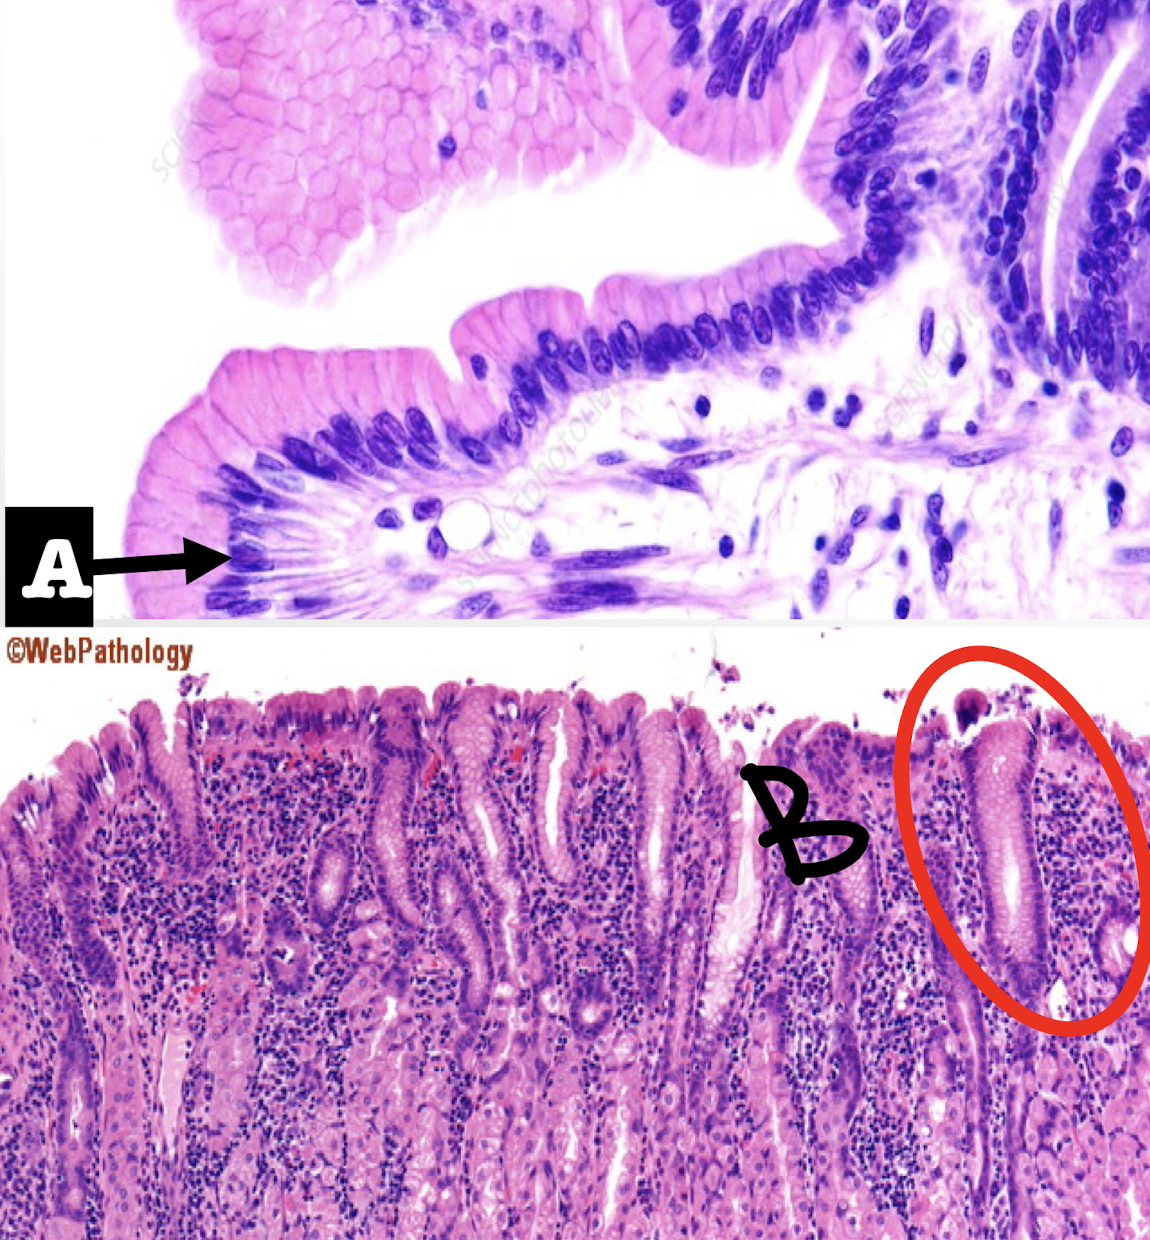

Recto-anal junction

A: rectum (simple columnar with goblet cells)

B: anus (stratified squamous non-cornified epithelium)

Identify the structure

rectum

Goblet cells are most numerous in this segment of the large intestine

rectoanal junction

simple columnar rectum to stratified squamous non-cornified anus